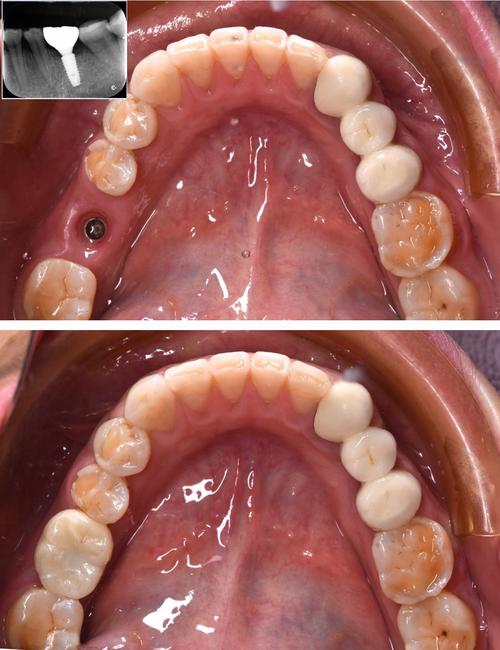

种植牙是通过外科手术将人工种植体植入牙槽骨,作为牙根支持牙冠,属于牙齿修复范畴,其疼痛感受主要来自手术创伤、术后恢复及骨整合期,具体可分为以下几个阶段:

骨整合期(3-6个月):轻微或无痛

种植体植入后需与牙槽骨结合(骨整合),此阶段无外部操作,种植体被骨头包裹,可能出现轻微异物感或咀嚼不适,但通常无疼痛,若骨条件差需植骨,植骨区域可能持续隐痛1-2周,但整体疼痛强度低于手术初期。

戴牙冠阶段:短暂不适

骨整合完成后,安装基台和牙冠时需切开牙龈(若埋入式种植),可能再次出现切口疼痛,但程度轻、持续时间短(1-3天),牙冠戴入后,若咬合过高,可能出现咬合痛,需医生调磨后缓解。